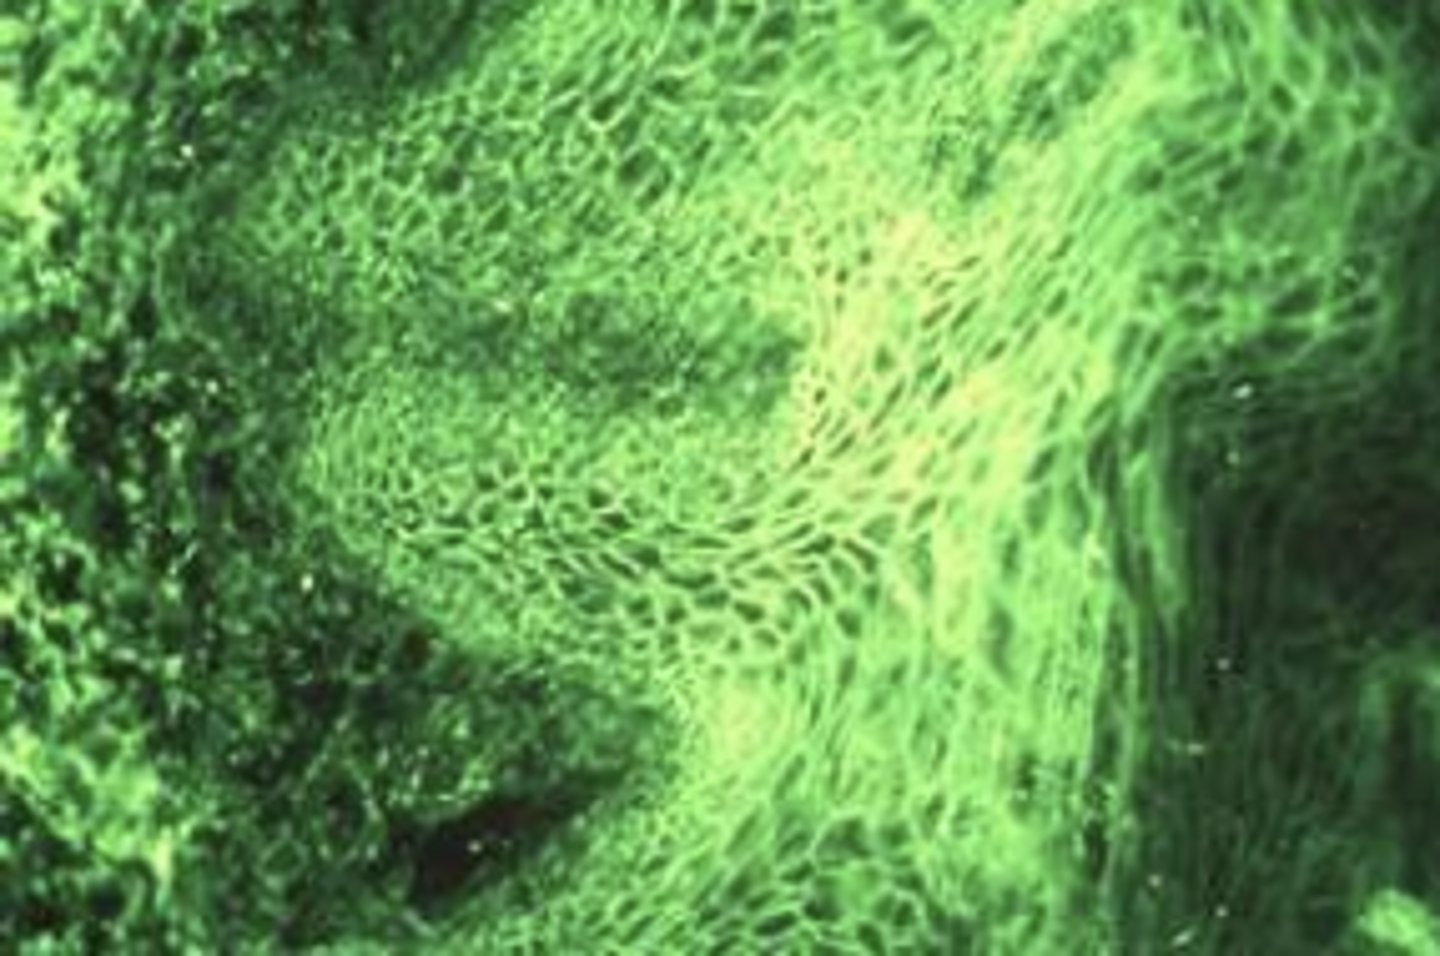

f. all of the above

Picture of inflammatory papillary hyperplasia. What are possible causes?

a. bad OH

b. negative pressure by form fitting denture

c. candida

d. A and B only

e. B and C only